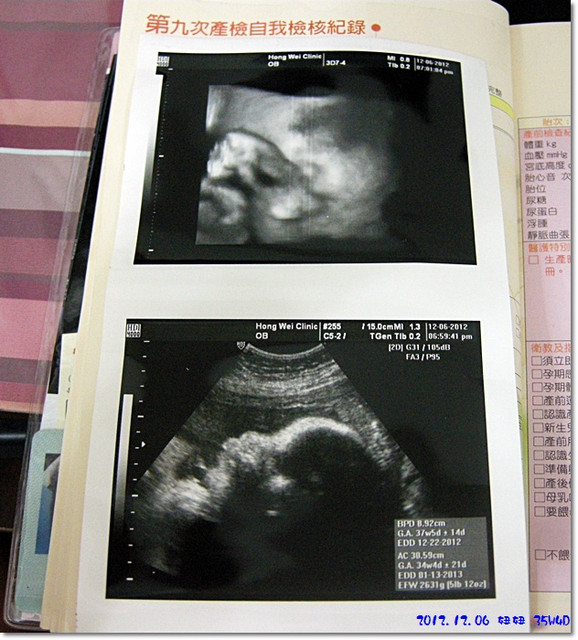

這是這次的超音波圖片...

多了上面那張,是因為陶醫師貼心的在百忙之中讓我們多看了一次3D![]()

目前35週,妞妞體重預估為2600g...

一個禮拜只多了100公克,尚可以接受啦(但麻咪好像覺得還是有點點少)